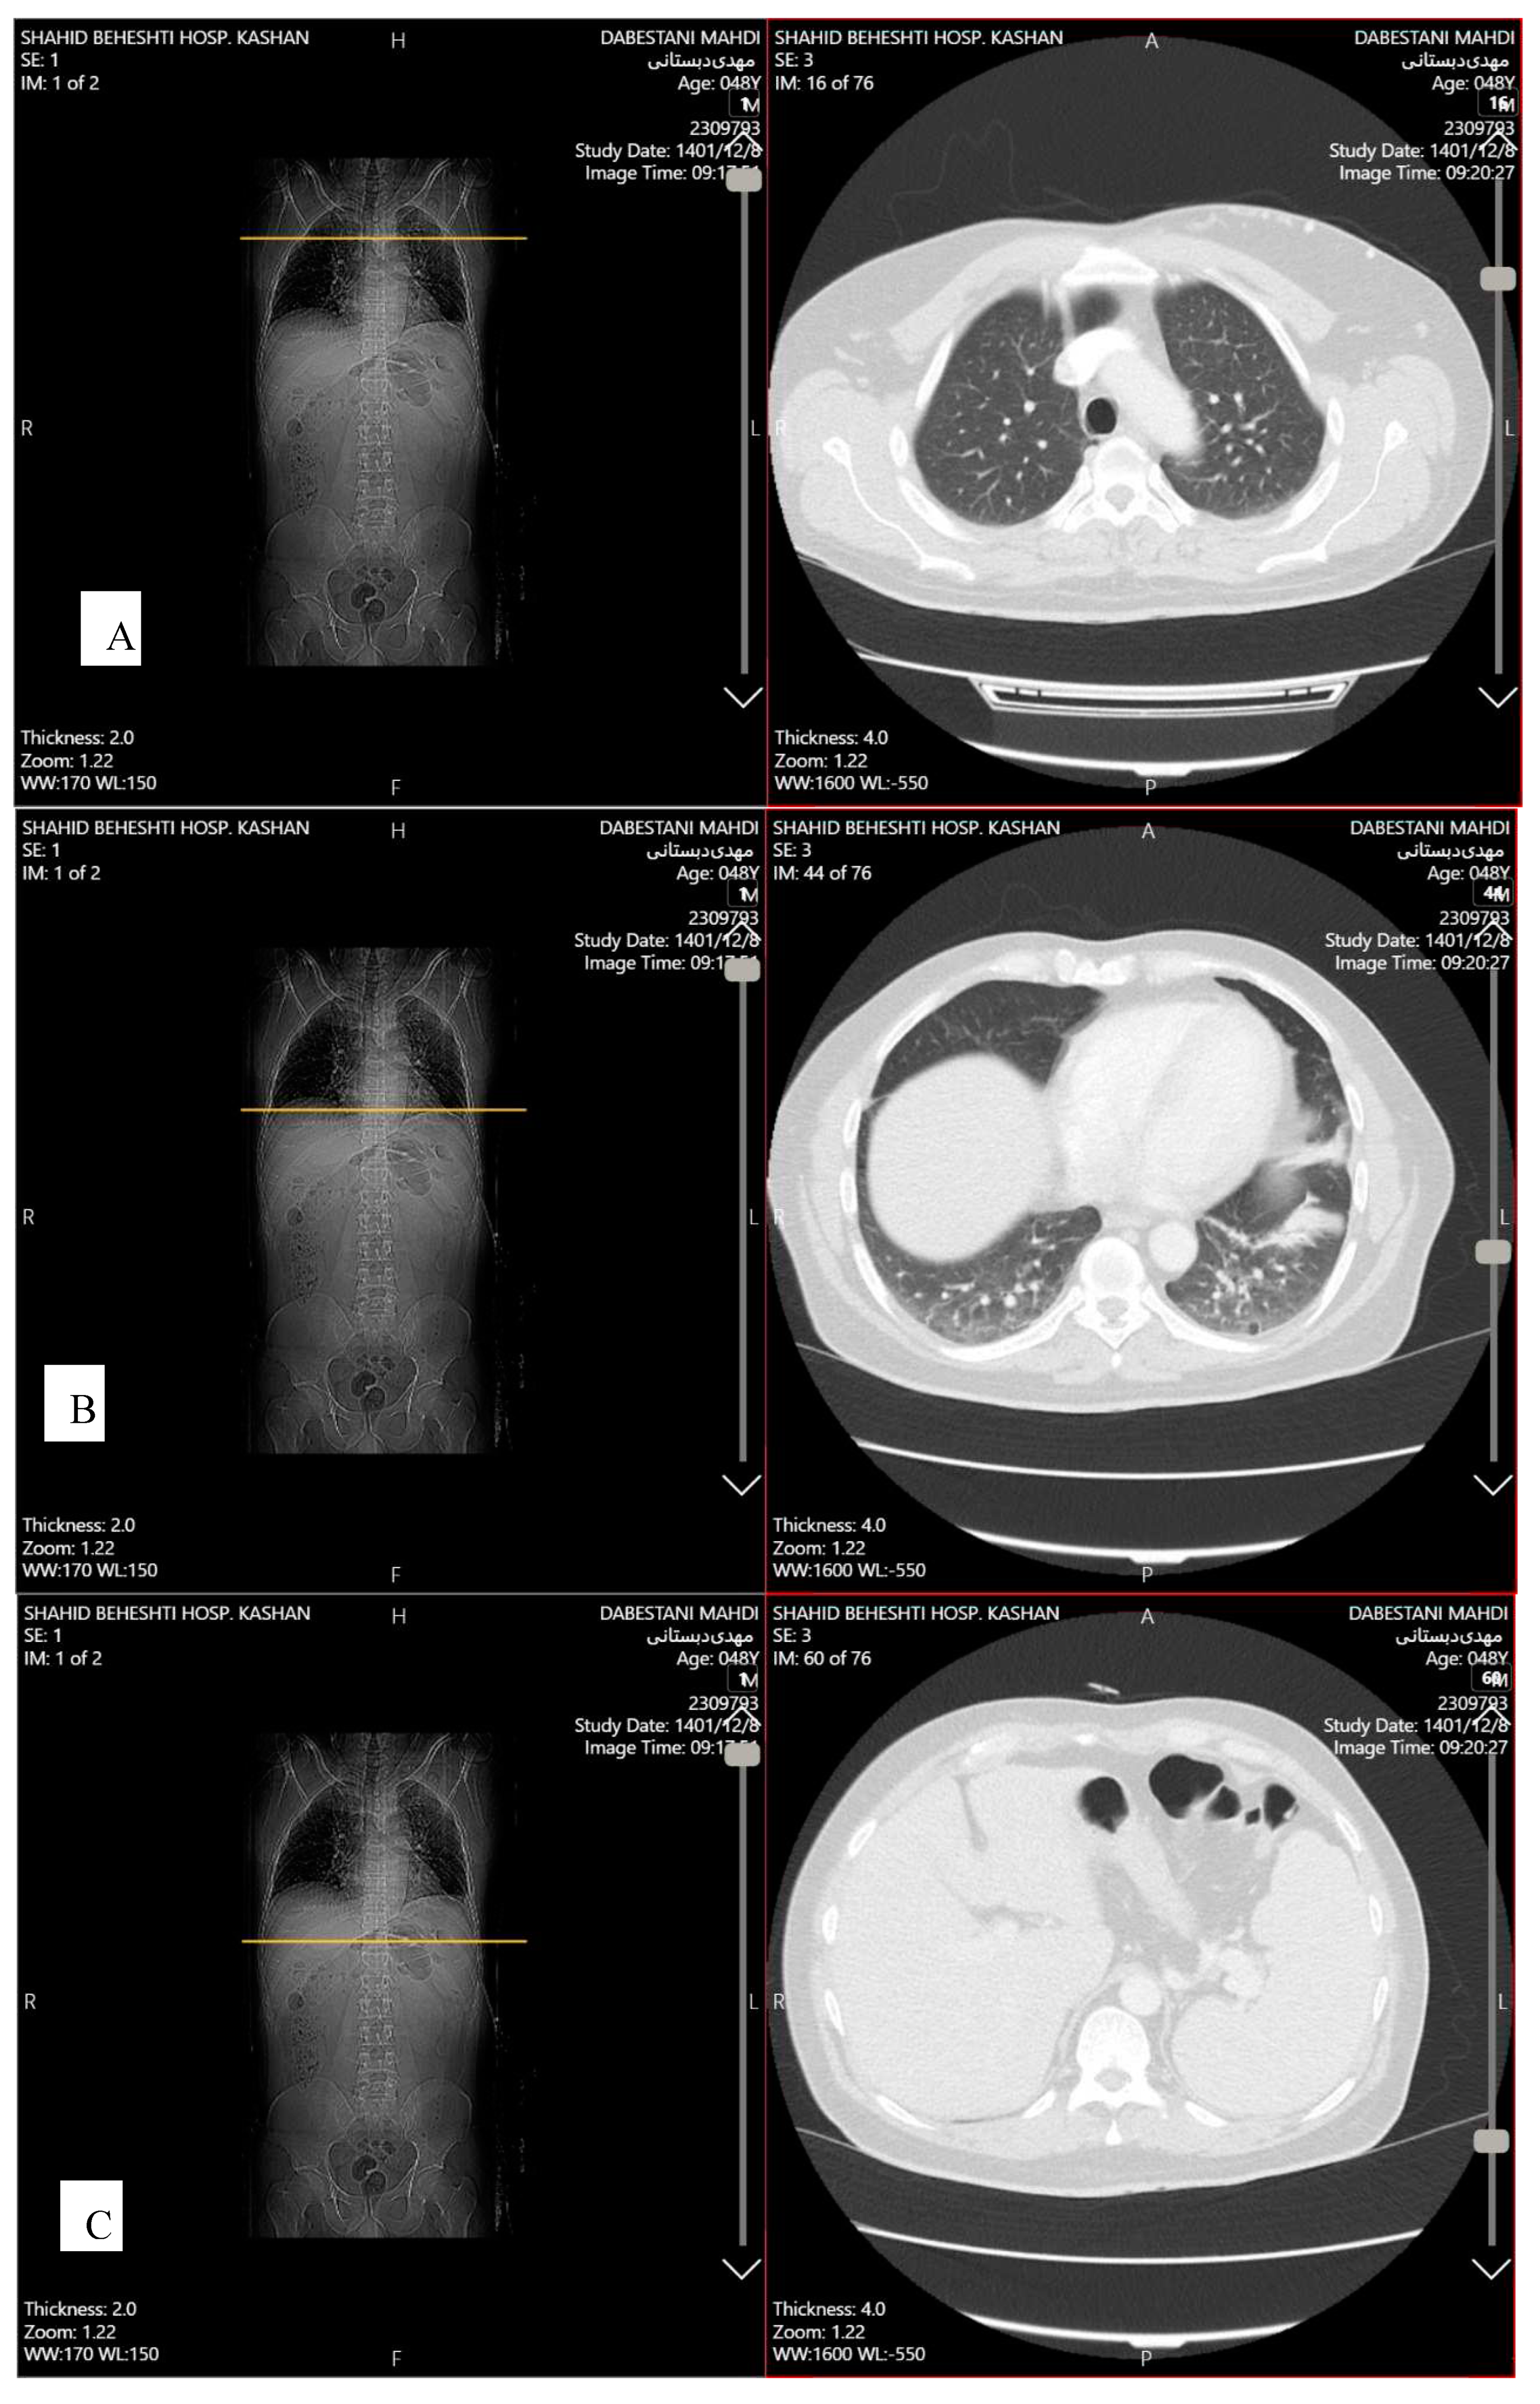

Transthoracic echocardiography (TTE) showed mild pericardial effusion, and mild diastolic dysfunction. Abdominopelvic spiral computed tomography (CT) scan with contrast demonstrated splenomegaly (135 mm). Chest spiral CT scan with contrast showed patchy collapse with features of air bronchogram in the right middle lobe, left hemidiaphragm elevation, diffuse discoid atelectasis in both lung fields with precedence in the left lower lobe and left upper lobe, multiple varicoid vessels on the left breast, aneurysmal vessels (7*12 mm) in lateral of left breast due to Mondor's disease, and mild fibrotic changes in the base of both lungs (Figure 2). Breast sonography was unremarkable.

Figure 2. Computed tomography scan of a 41-year-old male case of systemic lupus erythematous and antiphospholipid syndrome demonstrating (A) Diffuse atelectasis; (B) Patchy collapse with features of air bronchogram; (C) splenomegaly.